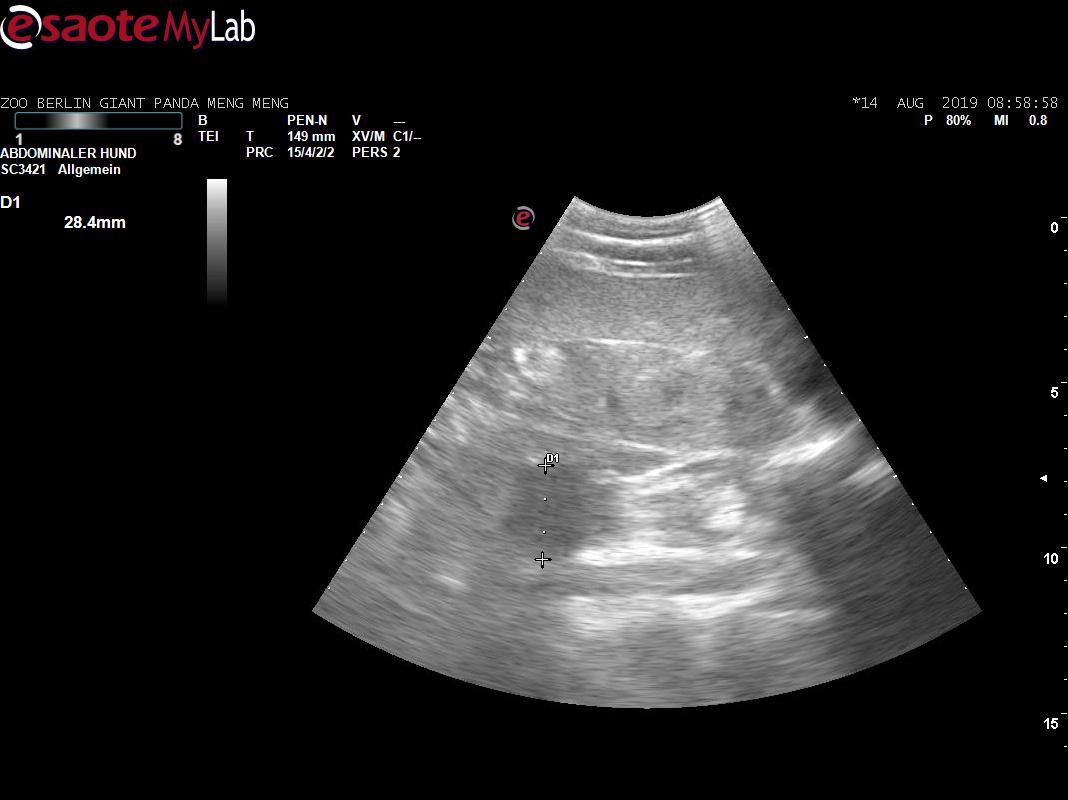

Зазначається, що експерти зоопарку та Інституту досліджень зоопарку та дикої природи Лейбніца змогли встановити вагітність Менг Менг лише за тиждень до пологів за допомогою УЗД.